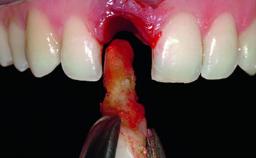

Replacement of an Ankylosed Upper Left Central Incisor: Bone Augmentation and Socket Grafting, Late Placement of an RC Bone Level Implant

Bone Augmentation Horizontal|Simultaneous|Staged

Augmentation Materials Autogenous chips|Xenogenous

Bone Volume Deficient horizontally, requiring prior grafting